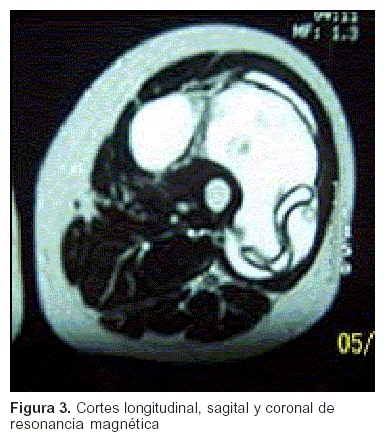

Mujer de 56 años procedente de medio rural, con antecedentes de quiste hidático pulmonar, operada a los 7 años. Hace 13 años consultó por tumoración de muslo izquierdo de 4 cm de diámetro, que fue interpretada como contractura muscular y medicada en forma sintomática. La misma se mantuvo estable, pero en el último año ha crecido en forma lenta pero sostenida, dolorosa al contacto, en los últimos meses le dificulta la marcha. Al examen, buen estado general, se destaca que el muslo izquierdo es francamente asimétrico (figura 1), con tumor firme y doloroso que compromete toda la logia antero externa, no móvil. No alteraciones motoras ni sensitivas. La tomografía computada (TC) muestra una extensa tumoración de partes blandas en logia de músculo cuadríceps, desde raíz de muslo hasta unión metáfiso-diafisaria inferior, hipodensa, polilobulada sin compromiso vascular, nerviosa o esquelética (figura 2). La resonancia magnética (RM) evidencia membranas intraquísticas características de quiste hidático (figura 3). Se realiza punción aspiración con aguja fina previo a la RM, que muestra quitinosa hidática. Eco Doppler de vasos femorales izquierdos normal. TC toracoabdominal, no muestra evidencia de hidatidosis. Serología para hidatidosis: positiva 1/2000.

Figura 3

Los estudios de uso sistemático son la ecografía y la tomografía(1,3,5), que tienen patrones bien definidos para las distintas lesiones (tabla 2); sin embargo, la RM representa un excelente método diagnóstico de imagen(16), que en nuestra experiencia ha demostrado ser de gran utilidad para establecer con mayor precisión el diagnóstico de hidatidosis, tanto en hígado como en partes blandas (figura 3).